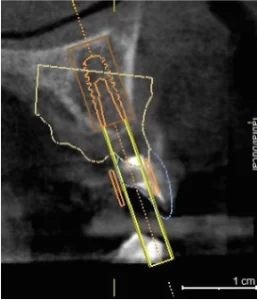

se realiza planeación quirúrgica computarizada, confección de guía de fresado y de provisionales acrílicos.

Zona postero superior derecha para aprovechamiento del hueso disponible y evitar elevacion de seno maxilar.